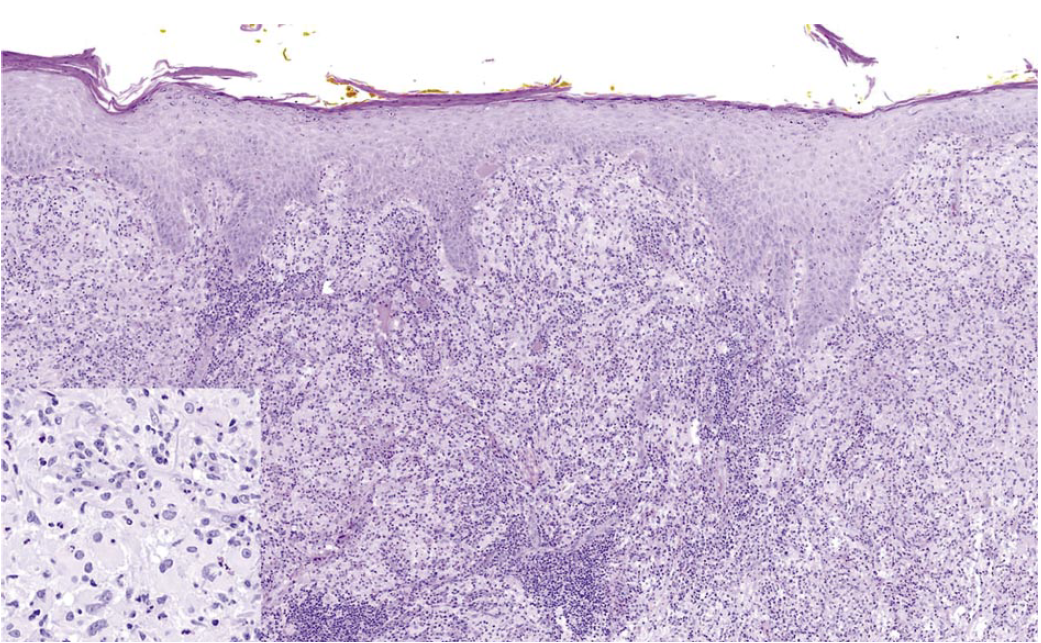

В октябре 2019 г. у мужчины 56 лет появилось опухолевидное образование на коже левой височной области. Через 3 нед опухоль радикально удалена. При гистологическом исследовании удаленного образования выявлена фиброзно-жировая ткань с хроническим гранулирующим воспалением. В течение 2 нед в зоне послеоперационной раны возобновился рост опухоли с появлением сливающихся папулезных высыпаний, которые распространились на кожу левой половины лица и волосистую часть головы. При повторном гистологическом исследовании в дерме обнаружился диффузный инфильтрат, состоящий преимущественно из гистиоцитов крупных размеров, гигантских клеток, небольшого количества плазматических клеток, скоплений лимфоцитов (рис. 1). При ИГХ-исследовании клетки гистиоцитарного ряда экспрессировали S100 (рис. 2), CD68, СD163 (рис. 3) и были негативны к фактору XIIIa, CD1a, CD123. При реакции с S100 визуализировались явления эмпериополеза (рис. 4). Таким образом, гистологические изменения и иммунофенотип клеток гистиоцитарного ряда соответствовали кожной форме БРД.

Рис. 1. Диффузный инфильтрат, состоящий преимущественно из гистиоцитов крупных размеров (вставка), гигантских клеток, небольшого количества плазматических клеток, скоплений лимфоцитов.

Fig. 1. Diffuse dermal infiltration mostly with large histiocytes (insertion), giant cells, few plasma cells, clusters of lymphocytes.